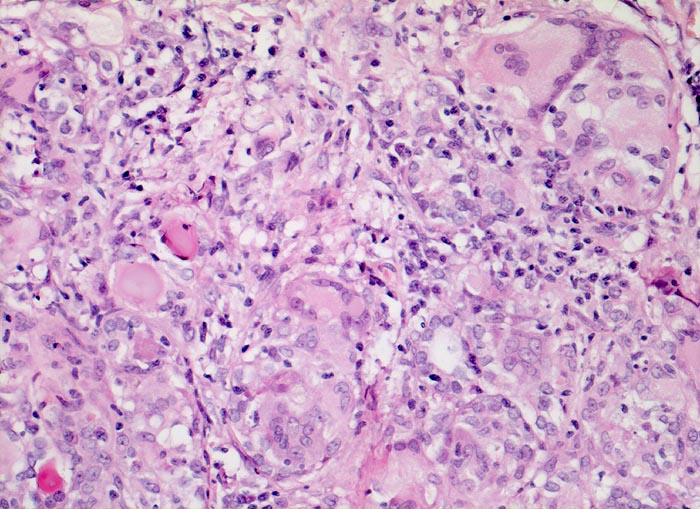

PathoPic ID 3779 - subakute Thyreoiditis de Quervain

subakute Thyreoiditis de Quervain

Entzündung / Reparatur

Schilddrüse

Endokrinium

Granulomatöse Entzündung aus Riesenzellen und Lymphozyten. Dazwischen teilweise zugrundegegangene Follikel.

Euthyreose und kalte Knoten in beiden Schilddrüsenlappen.

Histologie

200